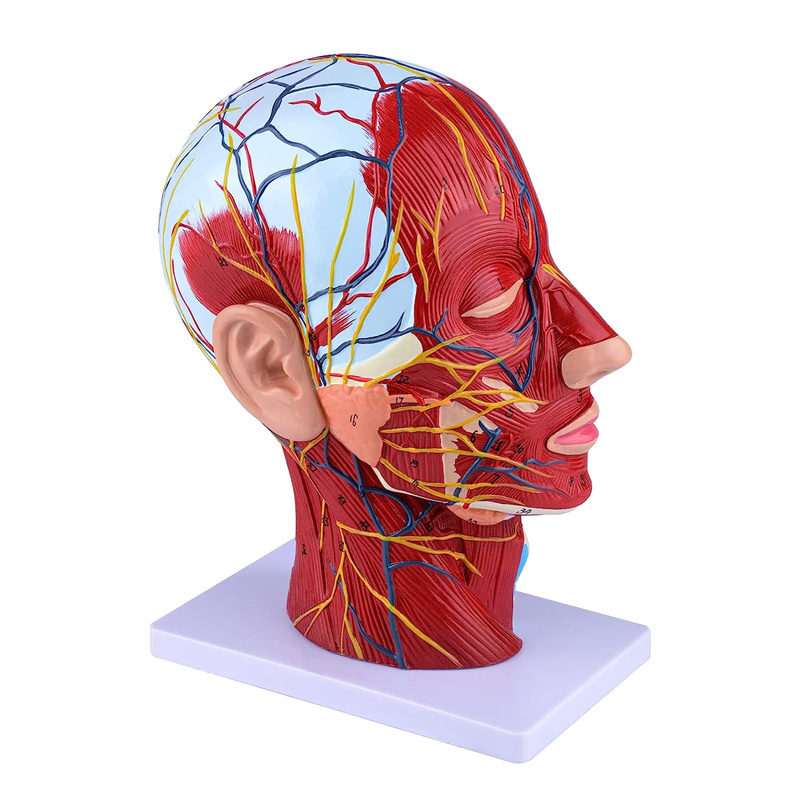

| Ciri -ciri | Model ini menunjukkan morfologi tempatan bahagian dalam dan luar bahagian median sagittal kepala dan leher, serta struktur saluran darah dan saraf, dan terdapat 84 bahagian yang menunjukkan tanda -tanda secara keseluruhan. |

【Model otot neurovaskular cetek】 Sangat terperinci, nombor yang ditandai, telinga boleh dilepaskan, memperdalam pemahaman otot, kapal, saraf dan struktur dalaman kepala & leher. Red-artery, biru-vein, kuning-saraf.

【Ciri -ciri】 Ia menunjukkan otot -otot cetek muka yang terdedah; saluran darah cetek & saraf muka & kulit kepala; struktur dalaman kelenjar parotid & saluran pernafasan atas; Struktur keratan rentas sagittal tulang belakang serviks.

Model ini menunjukkan butiran leher kepala kanan dan bahagian pertengahan sagittal manusia. termasuk cetek

otot muka yang terdedah; saluran darah dangkal dan saraf muka dan kulit kepala; struktur dalaman

kelenjar parotid dan saluran pernafasan atas; Struktur keratan rentas sagittal tulang belakang serviks.

Model ini menunjukkan morfologi tempatan bahagian sagittal medial dan lateral kepala dan leher dan struktur vaskular dan sarafnya, dengan jumlah 100 petunjuk tapak.

Model ini adalah model otot neurovaskular yang besar dan leher yang besar, 1 komponen, menunjukkan butiran kepala kanan dan leher manusia dan bahagian sagittal median, termasuk otot -otot dangkal yang terdedah pada muka, kapal cetek muka dan skalp, saraf, saraf, saraf, saraf, saraf, saraf, saraf, saraf, saraf, saraf, saraf, saraf, saraf, saraf, saraf, saraf, saraf, saraf, saraf, saraf, saraf, saraf, saraf, saraf, saraf, saraf, saraf, saraf, saraf, saraf, saraf, saraf, saraf, saraf, saraf, dan struktur medial kelenjar parotid dan saluran pernafasan atas, dan struktur bahagian sagittal tulang belakang serviks